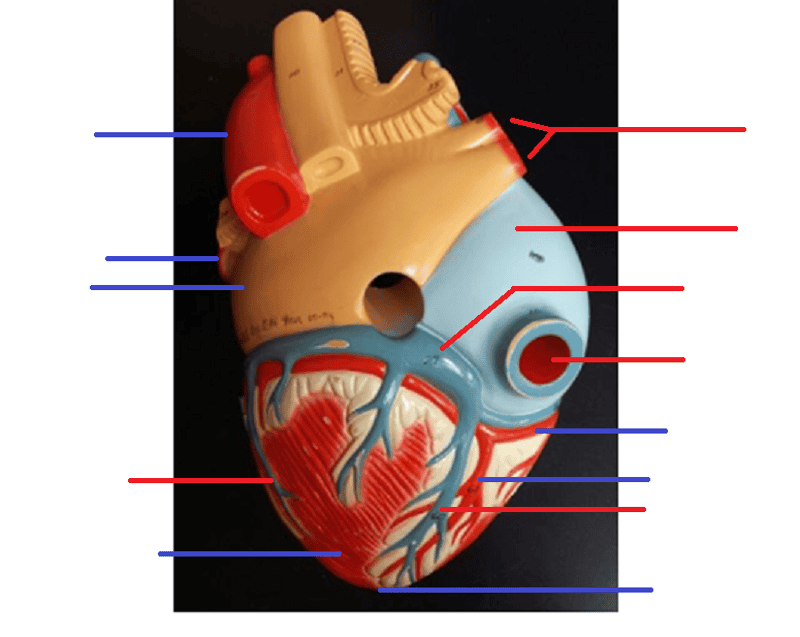

Name the missing parts.

Heart external anterior view